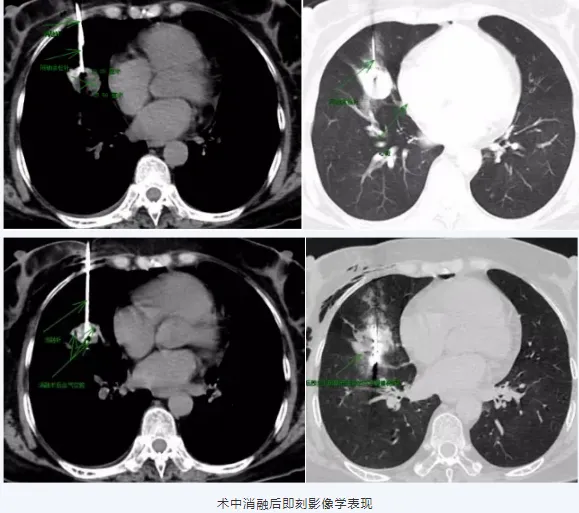

入院后,胸部增强CT检查显示:右肺中叶富血供病变,右肺中叶结节约2.6cmx2.2cm,考虑低度恶性肿瘤性病变。我院肺病科与影像科专家团队联合会诊,因患者在随访过程略增大,结合患者胸部增强CT不能排除低度恶性结节,现无法耐受手术,一直随访有发生突然增大及远处转移的可能,决定为患者实施CT引导下肺小结节穿刺活检同步微波消融术。“手术的难度较大,主要是结节位于中叶临近下叶斜裂处,跨叶间裂穿刺极易发生气胸和出血,一旦出血和发生气胸,都会掩盖肺小结节,导致穿刺失败,同时结节小且中叶呼吸动度大,结节距心脏近,穿刺有损伤心脏的风险。但为了患者的的健康,面对挑战,我们有信心搏一次。”肺病科主任谢加利介绍。

与患者家属沟通同意后,延安市中医医院肺病科谢加利主任、影像科王保奇主任、肺病科艾克东副主任、史悦主治医师组成专家团队,默契协作,成功为患者实施了CT引导下经皮右肺中叶结节穿刺活检同步微波消融术,获取病变组织样本,经病检确诊为硬化性肺细胞瘤。在医护人员悉心照料下,患者术后两天顺利出院,重展笑颜。